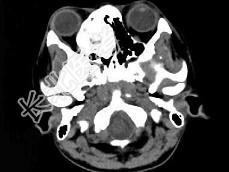

- 多项选择题女,18岁, 眼球轻度突出、眼痛、流泪近半年,CT扫描如图所示, 正确的描述或诊断是 ( )

A、右侧筛窦内见致密骨化影,鼻中隔向左偏

B、致密肿块影向右侧眼眶内突出,右眼内直肌受压

C、筛窦壁及鼻中隔未见骨质破坏

D、副鼻窦(筛窦)内骨瘤

E、副鼻窦(筛窦)内软骨瘤